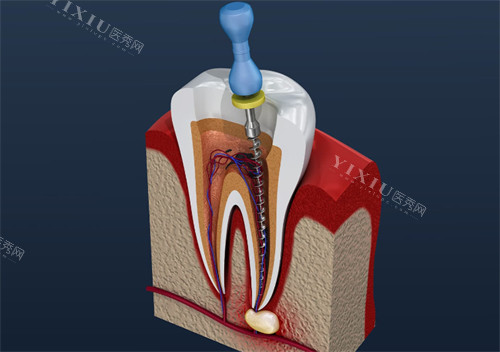

绍兴新昌青芸口腔补牙 / 根管治疗价格表:从浅龋到复杂病例

补牙和根管治疗是解决蛀牙、牙髓炎的常见项目,青芸口腔根据龋坏程度、材料选择,提供分层收费:

前牙根管治疗(单根管,含填充):800 元起

前磨牙根管治疗(双根管,含牙冠修复):1200 元起

磨牙根管治疗(三 / 四根管,复杂病例):1800 元起